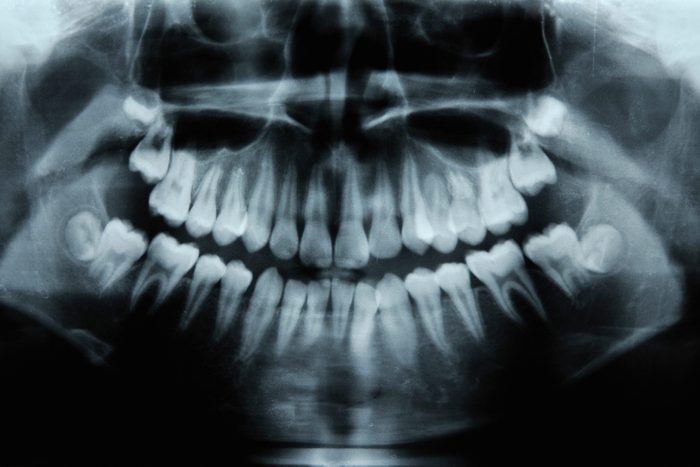

One dentist explains, 'Your mouth houses 700 species of microbes.' While not all of these are harmful, failing to brush your teeth can lead to serious health issues.

You’re likely aware that brushing and flossing are essential for preventing plaque and tartar buildup, reducing the risk of periodontal (gum) disease. However, what might not be as widely known is the extensive impact of good oral hygiene on your overall health. What happens when you don’t brush your teeth can lead to not only oral issues such as swollen, red gums, bleeding, pain when chewing, and loose teeth, but also serious complications for your heart, lungs, brain, and more.

This connection largely stems from the ecosystem within your mouth. “Your mouth houses 700 species of microbes, which includes germs like bacteria, fungus and more,” explains Joyce Kahng, DDS, Cosmetic Dentist and former Assistant Clinical Professor at the University of Southern California Herman Ostrow School of Dentistry. She continues, “Rest assured, not all microbes are badโin fact, some microbes are helpfulโbut it’s important to break up the biofilm routinely to prevent the unwanted microbes from creating an imbalance of the oral microbiome.”